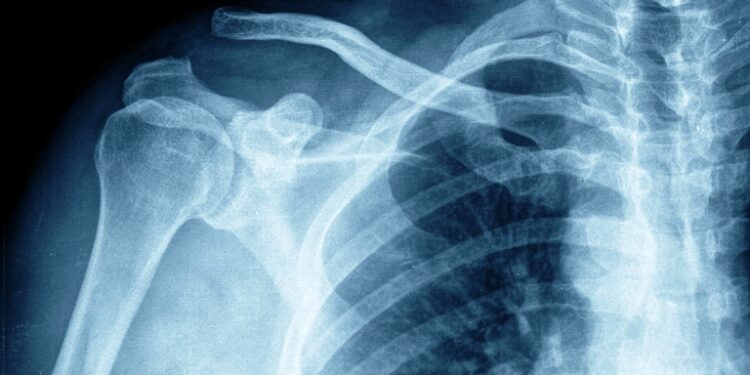

Na reclamação trabalhista, o empregado disse que fora admitido, por concurso público, para a função de carteiro e, após concurso interno, passou a carteiro motorizado. Em razão de fortes dores no ombro direito, realizou exames em que foi constatada lesão do manguito rotador, grupo de músculos e tendões da articulação do ombro, causada pelo levantamento de cargas.

O relator do recurso de revista do carteiro, ministro Alberto Bresciani, votou pela majoração do pensionamento vitalício para 100% do seu salário. Ele observou que o artigo 950 do Código Civil assegura às vítimas pensão que corresponda à importância do trabalho para o qual ficou inabilitado, na proporção da incapacidade, além das despesas com o tratamento e os lucros cessantes. No caso analisado, o TRT concluiu que o empregado, em razão das doenças apresentadas, está total e permanentemente incapacitado para a função de carteiro motorizado.